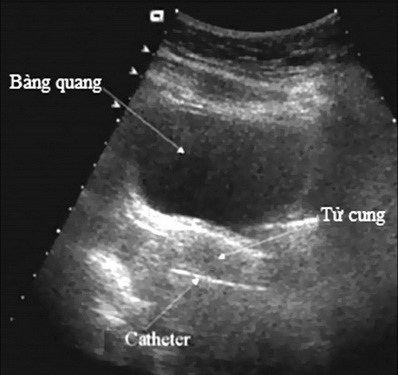

| Siêu âm giúp đo được kích thước tử cung bình thường hay nhi hóa. Ảnh: Sức Khỏe Đời Sống. |

Cách xác định tử cung nhi hóa chủ yếu dựa vào khám phụ khoa bao gồm âm hộ, âm đạo, tử cung và hai phần phụ có bất thường hay không. Siêu âm đo đường kính trước - sau của tử cung trên siêu âm và các triệu chứng khác như: đường kính tử cung có chỉ số dưới 30 mm. Trường hợp tử cung nhỏ hơn bình thường, phụ nữ vẫn thấy có kinh từ tuổi dậy thì. Trường hợp không có tử cung thường đi kèm bất thường bẩm sinh khác.